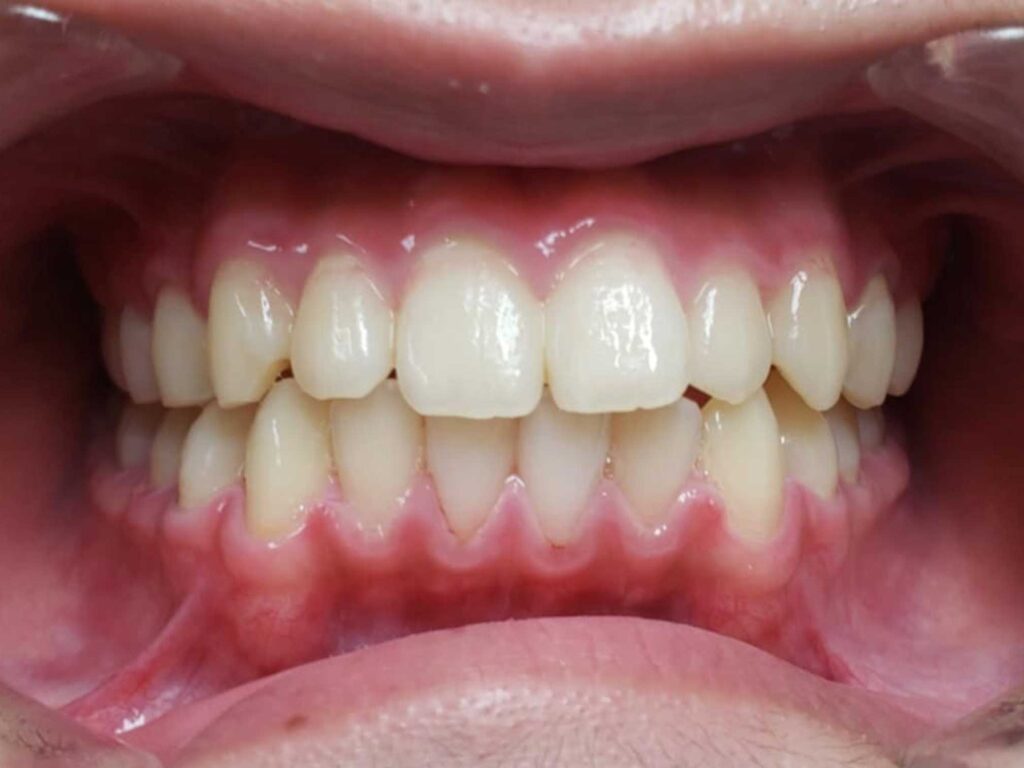

治療前

- 診断:1級咬合、左偏位、下永久歯(犬歯)萌出スペース不足

- 治療方針:非抜歯で行う。虫歯予防(フッ素)、歯磨き指導、舌位の改善、上下拡大床+補助断線→マウスピース矯正→下親知らずの抜歯、保定→メンテナンス